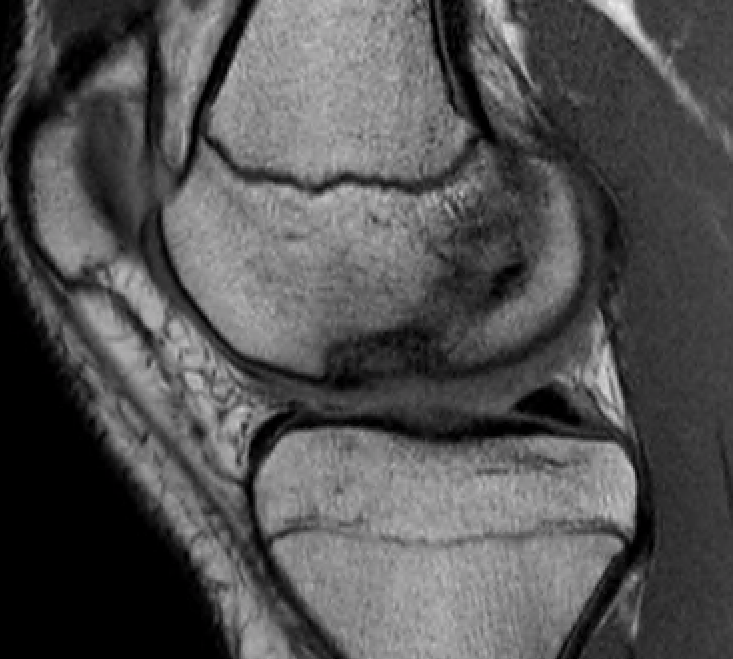

T1 sagittal on presentation T1 sagittal six months later

Progression of reossification over 6 months following drilling